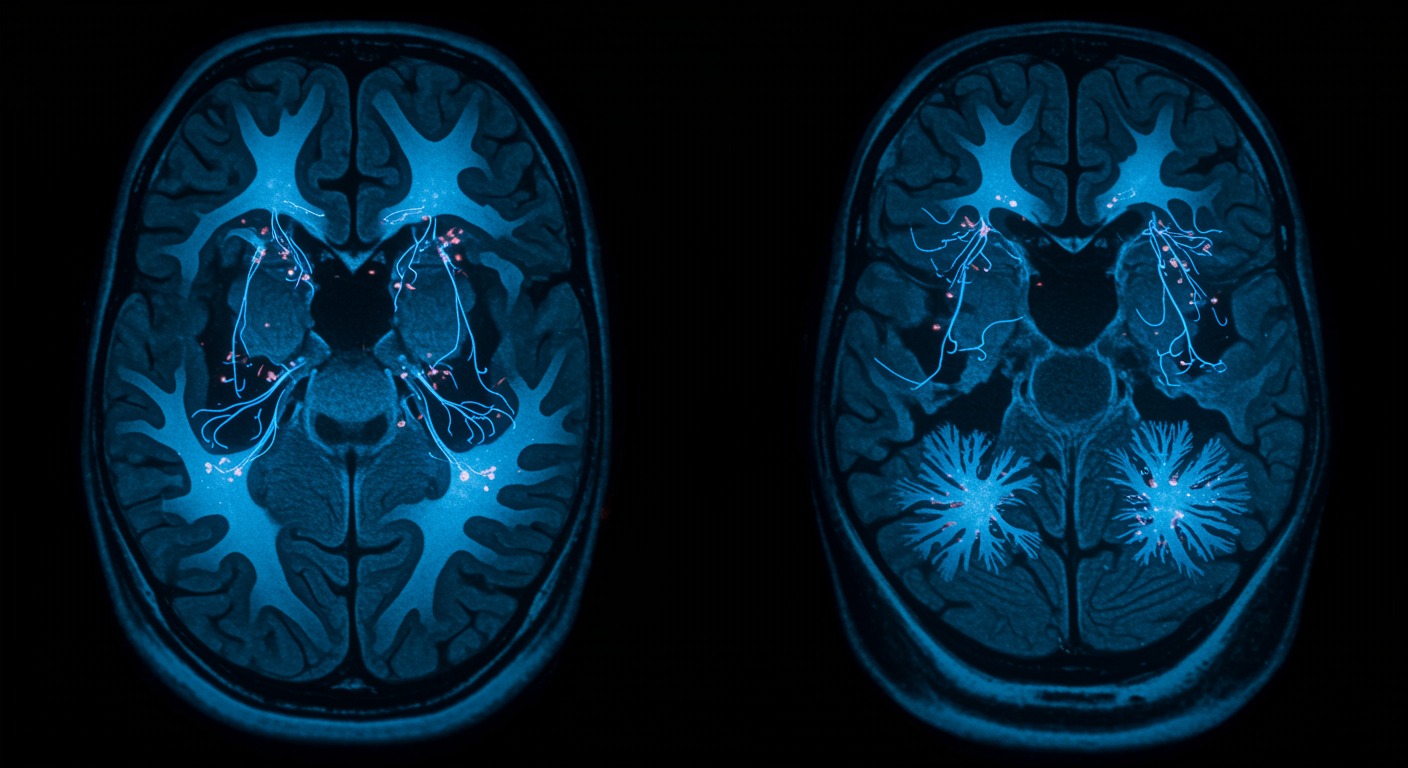

Loneliness creates measurable changes in brain structure and function, particularly affecting neural networks involved in social cognition, threat detection, and emotional regulation. These neurobiological changes help explain why chronic loneliness increases risks for depression, cognitive decline, and physical health problems, while also revealing potential targets for intervention.

Neuroimaging studies consistently demonstrate that loneliness alters brain activity and structure across multiple networks. The “social brain” - including regions like the anterior cingulate cortex, insula, and temporoparietal junction - shows altered connectivity patterns in lonely individuals. These changes affect how the brain processes social information, regulates emotions, and responds to stress.

Loneliness activates the brain’s threat detection systems while suppressing social reward circuits. The anterior cingulate cortex becomes hyperactive to social threats, while the ventral striatum shows reduced response to social rewards. This creates a neurobiological state of hypervigilance combined with reduced motivation for social connection - a pattern that can become self-perpetuating.